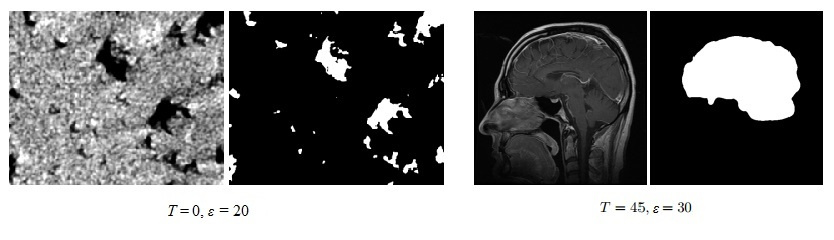

Например, если нам нужно выделить на изображении объекты с низким уровнем яркости (черные области), то $inline$T$inline$ выбирается равным нулю.

Слева выделяем черные области, справа — желаемая область имеет более большую яркость, поэтому выбираем $inline$T = 45$inline$